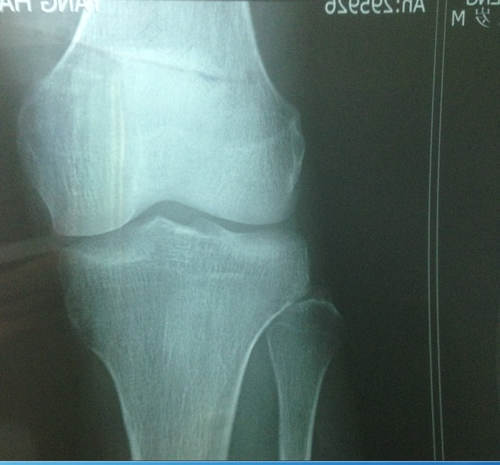

小孩子长骨的两头都有骨骺线,他是增长旺盛的骨组织,等孩子到了一定的年纪的时候,骨骺线就自然消失。就是大家所说的骨骺线闭合,实际上是说孩子长到一定的程度,就会失去自然成高的能力,性早熟的孩子,因为发育提前就会出现骨骺提前闭合。其中光照过度,就是诱发儿童性早熟的重要原因之一。